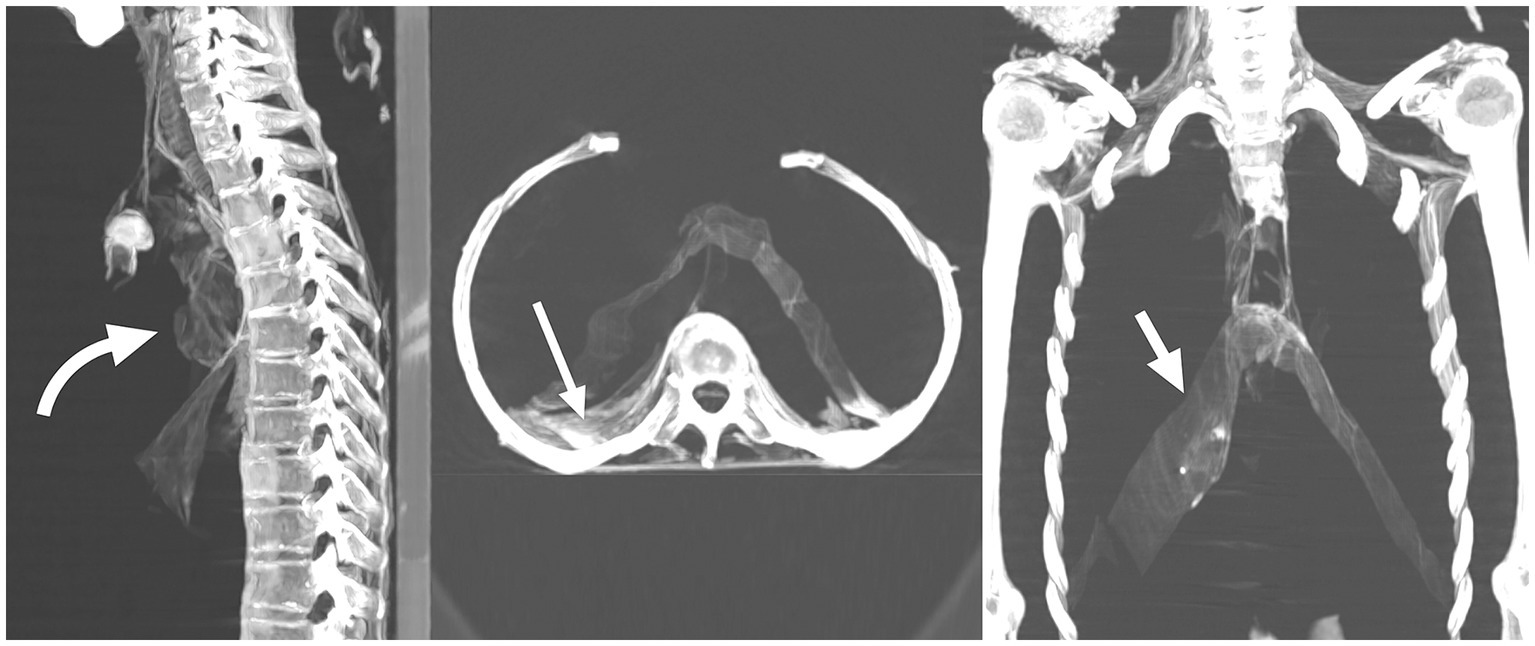

The interior of the torso contains shrunken desiccated structures including diaphragm, heart, and liver. Streaks of dried tissues are seen in the pelvic cavities. Torso cavity does not contain any foreign materials or packs. There are no openings or embalming incisions could be detected (Figure 7).

Figure 7

Multiplanar two-dimensional CT images of the torso of mummified woman CIT8 in sagittal, axial and coronal planes show presences of desiccated viscera: heart (curved arrow), abdominal viscera and liver (long straight arrow), and diaphragm (short straight arrows). Findings show no evisceration was done supported by the absence of an evisceration incision. The mummy was found at Luxor, Egypt, near Senmut’s service tomb, the architect during Queen Hatschepsut’s reign (1479–1458 BC).

Computed tomography scan of the mummified woman CIT8 shows no symptoms of evisceration; the torso cavity retains the desiccated viscera scoring 70% with Aufderheide’s visceral index, suggesting good preservation.

The use of CT imaging technology in the current study yielded important information regarding the mummy’s funerary treatment. Lack of evisceration in mummy CIT8, a procedure often associated with traditional New Kingdom mummification, implied that the embalming procedure was of low quality and that soft tissue preservation was achieved through natural mummification.